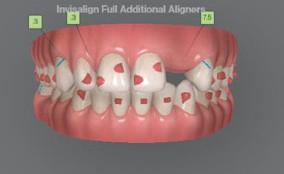

Dental Tribune Bulgarian Edition / октомври 2022 г.16 клиничен случай с алайнери Г орният латерален ре зец е вторият найчесто вродено липсващ зъб.1,2 Поради разполо жението му във видимата зона на усмивката лечение то на подобни случаи нала га мултидисциплинарен под ход, целящ отличен функцио нален и естетичен резултат. Налице са няколко лечебни мо далности, свързани с различ но разпределение на място то: първият вариант е орто донтско отваряне на място и възстановяване на липсва щия зъб с конструкция, под държана от съседните зъби3 или от имплант4, докато при втория подход разстоянията се затварят и премоларът заема мястото на канина.5 Изборът на лечебен подход трябва да бъде направен съв местно от зъболекар и паци ент въз основа на очакванията на последния и предвиди мостта на лечението. Множе ство фактори влияят върху това решение, като напри мер типа малоклузия, размера, формата и цвета на кучеш ките зъби6, оклузалните вза имоотношения (овърджет и овърбайт), лицевия профил, дължината на зъбната дъга и несъответствията в разме ра на зъбите.7 В настоящата публикация се разглежда случаят на жена в зряла възраст с вродена лип са на горен ляв латерален резец. Бяха приложени про зрачни алайнери за отваряне на място за единичен им плант и бяха постигна ти функционална оклузия и отлична естетика. ПРЕДСТАВЯНЕ НА СЛУЧАЯ Диагноза Пациентката бе на 32 годи ни, когато лечението започна, и първоначалното ѝ състоя ние бе следното (фиг. 1–3): липсващ горен ляв латерален резец; клас II, подклас I малоклузия; отклонение на горната сре динна линия вляво; Доклад на клиничен случай ЛЕЧЕНИЕ С АЛАЙНЕРИ НА ПАЦИЕНТ С АГЕНЕЗИЯ НА ЛАТЕРАЛЕН РЕЗЕЦ Д-р Iro Eleftheriadi и д-р Christodoulos Laspos, Гърция и Кипър Фиг. 1a–h Предоперативни лицеви и интраорални снимки. Фиг. 2a–e Дигитални модели преди началото на лечението. Фиг. 3 Панорамна снимка преди лечението. Фиг. 1a Фиг. 1d Фиг. 1f Фиг. 2a Фиг. 2d Фиг. 2b Фиг. 2e Фиг. 3 Фиг. 2c Фиг. 1b Фиг. 1e Фиг. 1g Фиг. 1h Фиг. 1c

Dental Tribune Bulgarian Edition / октомври 2022 г. 17клиничен случай с алайнери леко струпване в долната че люст; несъответствие по Болтън (мандибуларен излишък от 3.06 мм във фронталната зона и общо 1.47 мм); издължено лице с лицева аси метрия; конвексен профил с ретруди рана долна челюст и проми нентен нос. На мястото на зъб #46 бе на лице имплант, а зъби #16 и 26 са ендодонтски лекувани. Тези зъби бяха асимптоматич ни, затова бе взето решение да се прави релечение само при нужда. Мъдреците липсваха. Анализът на телерентгеногра фията (фиг. 4) показа ретрог натна мандибула (SNB: 74.2°) и нормална инклинация на резците както в

Цели на лечението и лечебен план Целите на лечението бяха следните: нивелиране и подреждане на зъбите и в двете зъбни дъги; отваряне на пространство за липсващия латерален резец; коригиране на отношенията при канините и моларите до клас I; и корекция на отклонението на срединната линия. Лечебният план включваше: корекция на отношенията при кучешките зъби и мола рите до клас I с дистализира не на максилата; отваряне на пространство в областта на #22 за поставя не на единичен имплант; корекция на срединната ли ния; и създаване на място за раз ширяване на зъб #12 и апрок симална редукция в долната челюст с цел подобряване на несъответствието по Болтън и осигуряване на подобра оклузия. Изпълнение на лечебния план Този случай бе изпълнен със системата за алайнери Invisalign (Align Technology). Одобреният първоначален лечебен план предвиждаше 49 алайне ра с дистализиране на задни те горни зъби до клас I (прибли зително с около 3.5 мм; фиг. 5). За бъдещия имплант в областта на липсващия латерал бе планирано пространство от 6.5 мм, докато във фронталния сегмент на долната челюст бе предвидена апроксимална редук ция. В дясната страна бутон за ластици клас II бе поставен на зъб #47 вместо на зъб #46, за да не се увреди короната на импланта. Понеже пациентката жи вееше в чужбина,

следните казуси: недобра оклу зия в дисталните зони по вре ме на дистализирането на гор ната челюст и накланяне на зъб #21 (фиг. 7). Последното се дължи на липсата на компози тен атачмънт на този зъб, каквото не бе зададено в пър Фиг. 4 Телерентгенография и цефалометричен анализ преди началото на лечението. Фиг. 5a–e Одобреният първоначален лечебен план. Фиг. 6a–h Снимки по време на лечението, показващи нуждата от внасяне на някои корекции. Фиг. 4 Фиг. 5a Фиг. 5d Фиг. 6a Фиг. 6d Фиг. 6f Фиг. 6b Фиг. 6e Фиг. 6g Фиг. 6h Фиг. 6c Фиг. 5e Фиг. 5b Фиг. 5c

Dental Tribune Bulgarian Edition / октомври 2022 г.18 воначалния план. Тези пробле ми бяха адресирани чрез допъл нителна поръчка на алайнери с торк контрол и зададено екст рудиране на задните зъби с цел установяване на добри оклузал ни контакти в дисталните об ласти, като бяха предвидени и оптимизирани атачмънти с контрол над корените за корекция на ангулацията на макси ларните резци (фиг. 8). Резултати от лечението Панорамната рентгено графия след ортодонтското лечение показа благоприятна паралелна позиция на съседни те зъби, подходяща за поставя не на имплант в областта на #22, както и конвергенция на ко рените на зъби #44 и 45 (фиг. 9), но преценихме, че няма да от деляме допълнително лечебно време за коригирането ѝ поради факта, че пациентката бе мно го доволна от постигнатия до момента резултат. След при ключване на лечението бяха постигнати отлични взаимо отношения клас I при мола рите и канините, а срединни

ти и клас II ластици е устано вено, че осигурява достатъч на дистализация без промяна на лицевата височина.23 Както се видя от цефалометричния анализ, точно това бе постиг нато и в представения случай като се има предвид, че лице вата височина остана същата като първоначалната. Предвид леката тенденция към дистал Фиг. 8a–e Поръчаните допълнителни алайнери. Фиг. 9 Панорамна рентгенография след края на лечението. Фиг. 10a–c Странични (а и с) и фронтална интраорални снимки след края на ортодонтското лечение и поставянето на импланта (b). Зъб #12 все още не беше протезиран. Фиг. 11а и b Оклузални снимки след ортодонтското лечение. Фиг. 7a Фиг. 8a Фиг. 7d Фиг. 8d Фиг. 9 Фиг. 10a Фиг. 10b Фиг. 10c Фиг. 11bФиг. 11a Фиг. 7b Фиг. 8b Фиг. 7e Фиг. 8e Фиг. 7c Фиг. 8c Фиг. 7a–e Интраоралната ситуация по време на лечението. клиничен случай с алайнери